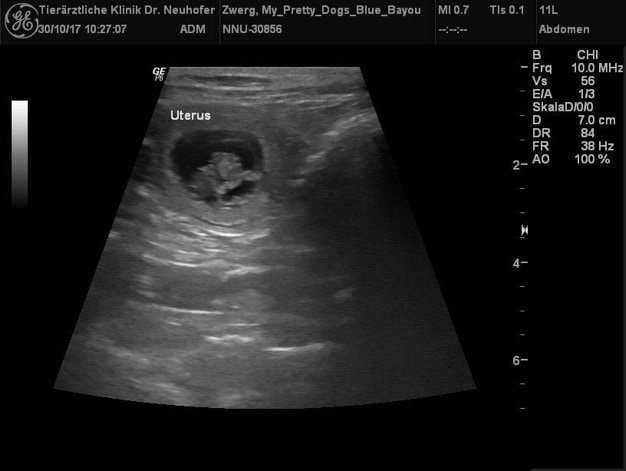

Es hat geklappt!!!! RTCH2 JB Black Saphires Take a Chance und

Ch. My Pretty Dogs Blue Bayou erwarten ebenfalls wundervolle Welpen in Bi und Tri um den 5. Dezember herum.

Blue Bayou und ich waren am 2.10. in Dolgesheim beim Rüden Chance. Die beiden haben sich auf Anhieb verstanden und Hochzeit gefeiert.

Nun heißt es warten und Daumen drücken.